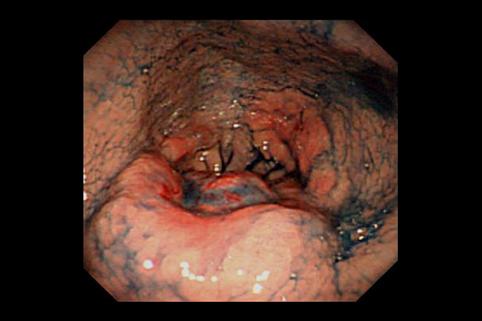

A case of type 5 advanced gastric cancer which developed in the antrum and was diagnosed by multidisciplinary method.

[Image-ID:11380]

Tumor Epitelial Maligno/Adenocarcinoma

estómago(región)/antro

Endoscopia

Tipo 5(no clasificable)/

40 -

s(a)